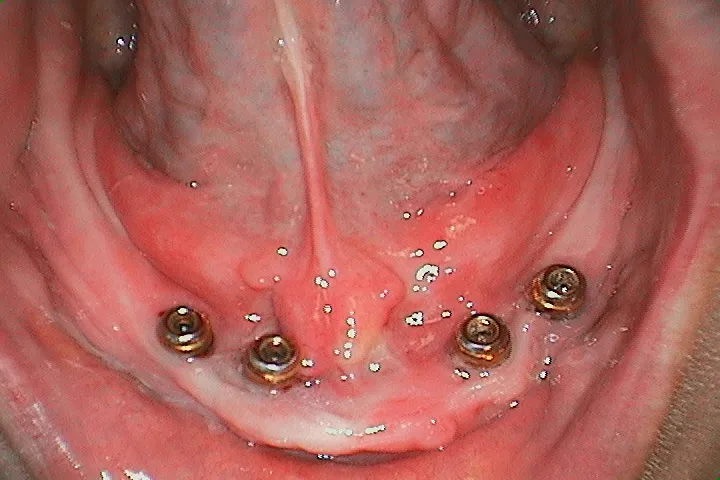

オールオン-4

前![オールオン4配置]()

後![All-on-4 配置後のケース 1]()

後![All-on-4 配置後のケース 2]()